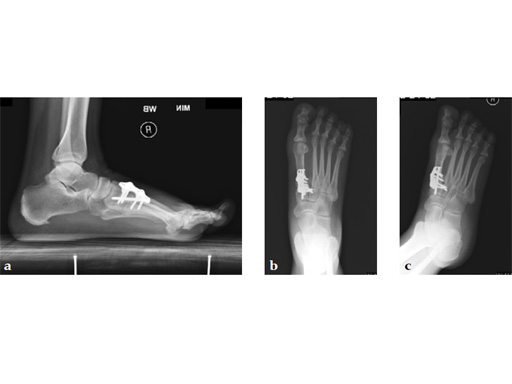

Case 2: First MTP fusion plate

A 38-year-old man presented for opinion after two attempts to fuse the big toe MTP joint. The AP view is significant for luscency at the joint line. The lateral view is notable for loosening of the hardware and malposition because of the dorsiflexion built in to the precontoured implant. Revision was planned using a 0 variable angle locking/compression hallux MTP plate.

At 10 weeks postoperatively (see Fig. 2ab) the patient had no pain with weight bearing. The lateral view demonstrates improved position of the toe using a 0angle plate.